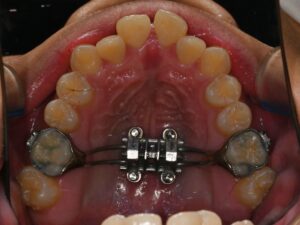

중랑구 교정치과 골격성 3급 부정교합, MARPE 상악 확장장치를 통한 개선

안녕하세요, 중랑구 교정치과 김정은원장입니다. 24.10.18 정면에서 보았을 때 턱의 위치가 옆으로 기울어져 보이거나 위아래 앞니의 중심선이 맞지 않는 느낌이 든다면 신경이 쓰일 수 있습니다. 이러한 안모 비대칭은 단순한 배열의 문제가…